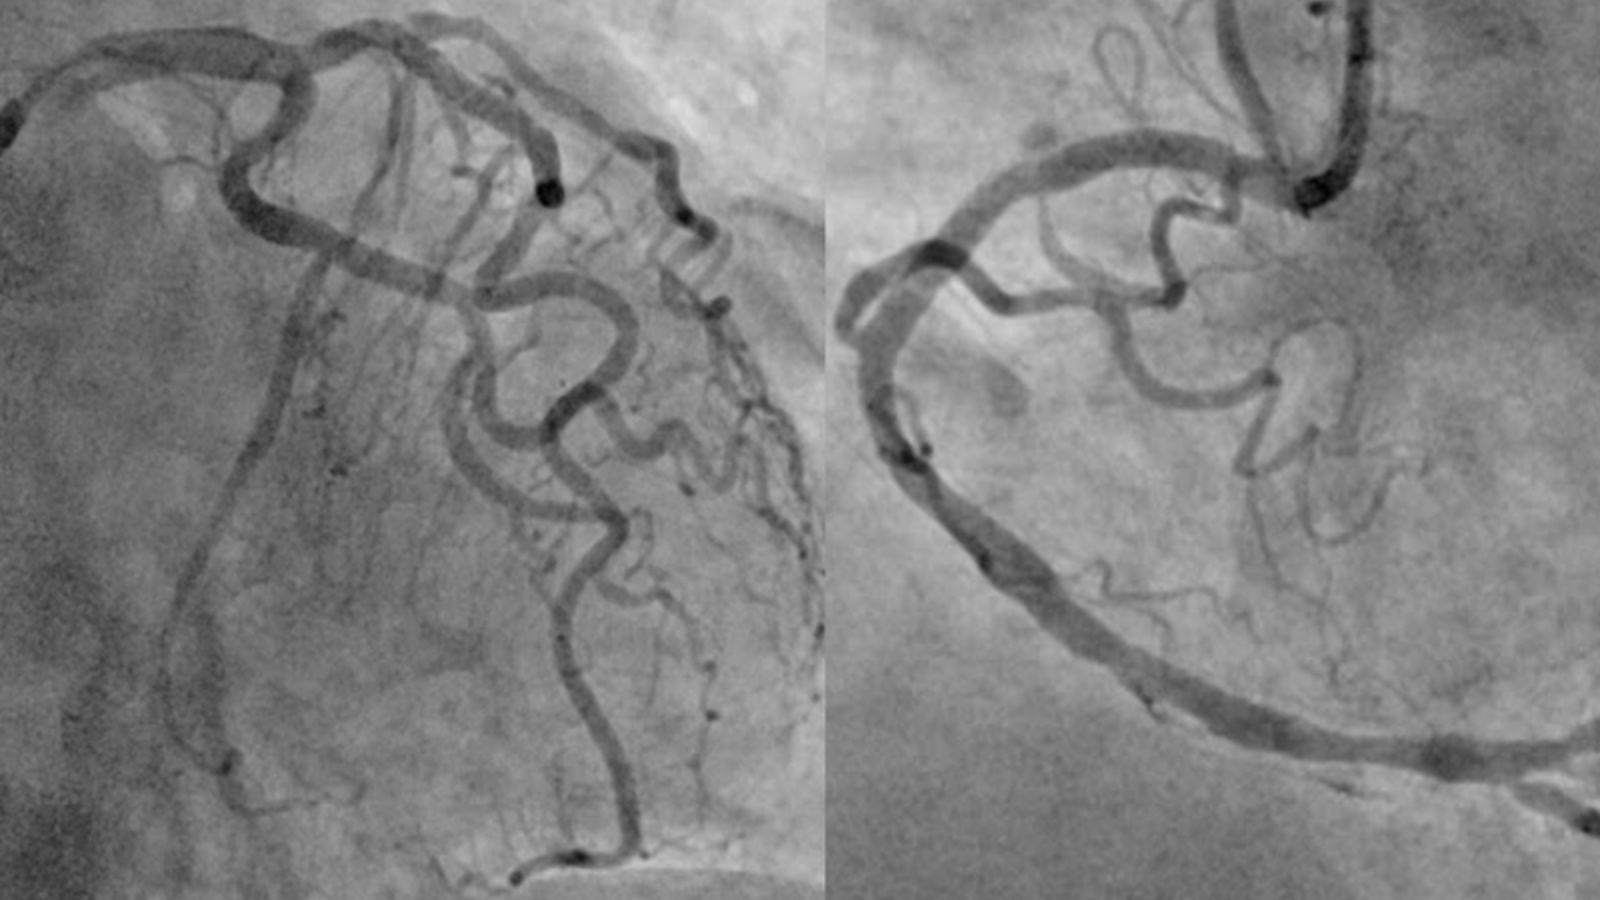

Hình ảnh mạch vành của người bệnh sau khi đã được can thiệp tái thông toàn bộ các động mạch vành tắc và hẹp.

Sau khi giải thích kỹ chẩn đoán, định hướng điều trị, các lợi ích và nguy cơ của thủ thuật cho người nhà, người bệnh lần lượt được can thiệp nong bóng và đặt stent thành công cả ba nhánh động mạch mũ, động mạch liên thất trước và động mạch vành phải. Người bệnh sau đó được chuyển lên khoa Hồi sức tích cực – chống độc để tiếp tục điều trị.